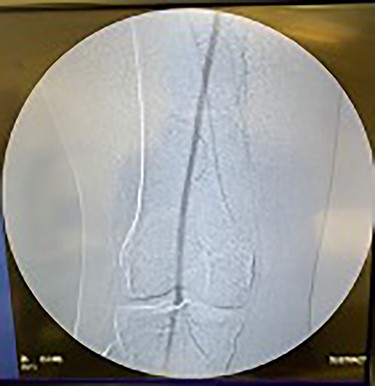

Lastly, the right iliac artery (Fig. 5) was treated using the same method (Fig. 10). After completion of the angioplasty procedure, catheter arteriogram was repeated to visualize the effectiveness of the procedure in relieving the extensive stenosis. The imaging revealed almost complete restoration of the diameter of both left and right iliac arteries (Figs 11 and 12). The distal aorta also showed improved diameter after the procedure (Fig. 9). Angiogram of both lower extremities was also performed. The catheter was passed distal to the stenosis that was previously present in the left iliac artery, to help visualize perfusion of its distal branches (Figs 13 and 14). The catheter was removed from the right femoral artery and reinserted in a distal fashion, to help visualize downstream perfusion. The right popliteal artery was well visualized on angiogram (Fig. 15), signifying strong perfusion. The patient was strongly advised to discontinue smoking cigarettes. In addition, the patient was advised to maintain regular physical exercise as tolerated and take baby aspirin daily to prevent thrombotic events.

Fluoroscopy showing dilation of the right iliac vessel post-angioplasty.